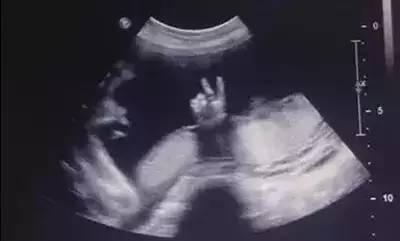

当然,这张B超图里,这位调皮的宝贝正在“噢耶”,看来已经迫不及待想出来见见世界了呢!